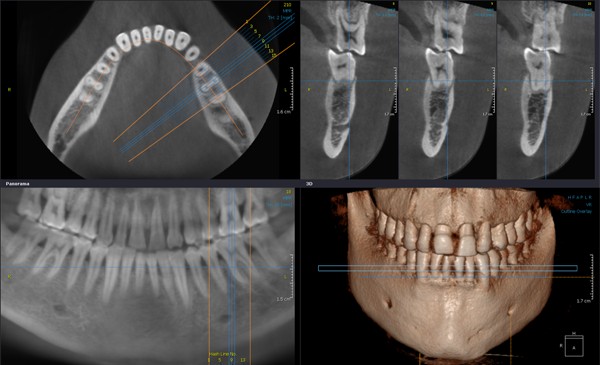

К счастью, в современной стоматологической диагностике, и в нашей клинике в частности, используются специализированные дентальные томографы. Это оборудование не только позволяет получать высокоточные снимки с толщиной среза 0,15-0,3мм, но и создавать 3D-модель сканируемой области. Имея такую информацию, стоматолог получает возможность изучить необходимый участок зубочелюстной системы под любым углом и с любой точки зрения и правильно составить дальнейший план лечения. Программа точно воссоздает все необходимые данные: форму, расположение, строение и размеры элементов челюстно-лицевой области.